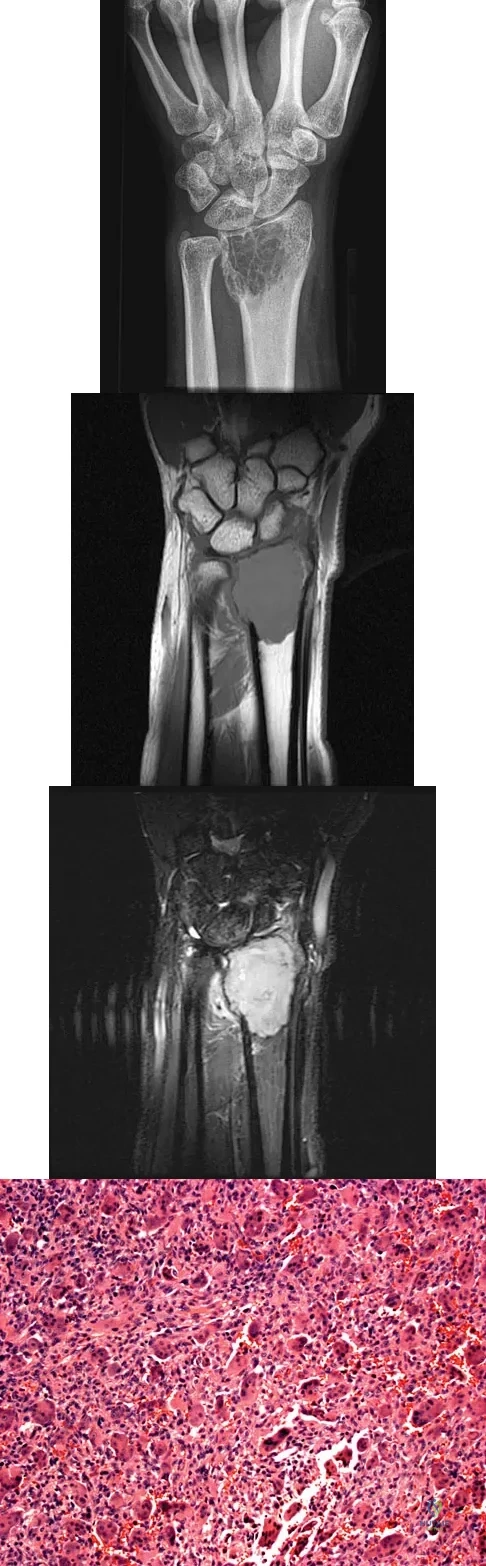

A 20-year-old woman has had wrist pain for the past 5 months. A radiograph, MRI scans, and biopsy specimen are shown in Figures 46a through 46d. The patient is then treated with intralesional surgery. The patient should be counseled that her risk of developing lung metastasis is approximately what percent?

An 83-year-old woman reports pain in her left middle finger after a minor injury. Laboratory studies show a WBC count of 7,000/mm3, an erythrocyte sedimentation rate of 3 mm/h, a uric acid of 10.4 mg/dL, and a normal serum protein electrophoresis. Radiographs are shown in Figures 49a and 49b. A core biopsy specimen is shown is Figure 49c. In addition to treatment of the finger fracture, treatment should include

A 21-year-old man has had right groin pain for the past year. A radiograph, CT scan, MRI scans, and a biopsy specimen are shown in Figures 50a through 50e. What is the most likely diagnosis?

A 10-year-old boy has had wrist pain for the past 3 months. He denies any history of trauma. He reports mild tenderness associated with a palpable mass. A radiograph and biopsy specimens are shown in Figures 52a through 52c. What is the most likely diagnosis?